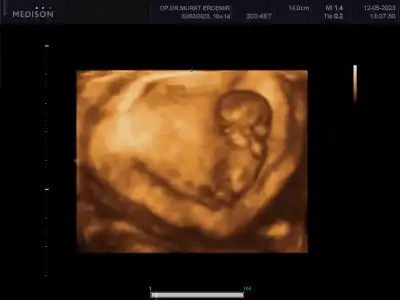

Bu arada son ultrason videosundan bir kesit gönderiyorum. Nub u şu altta görünen sanırım bizim oğlanın 😃 karşıya doğru uzayan şey sanırım ama bilemedim

Eklentiler

• IMG_8288.webp

IMG_8288.webp

12,9 KB · Görüntüleme: 84